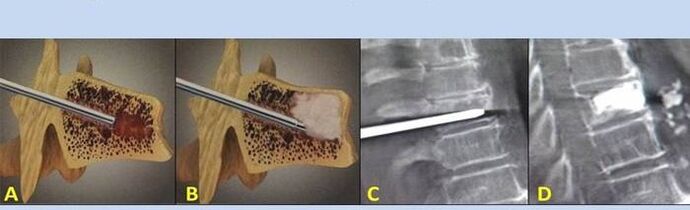

- Nucleoplasty– removal of the core of the intervertebral disc.The surgery relieves the pressure on the nerve endings.

- Stab vertebroplasty– the method of stabilizing the vertebrae.During the procedure, the doctor fills the cavities of the spine with bone cement.